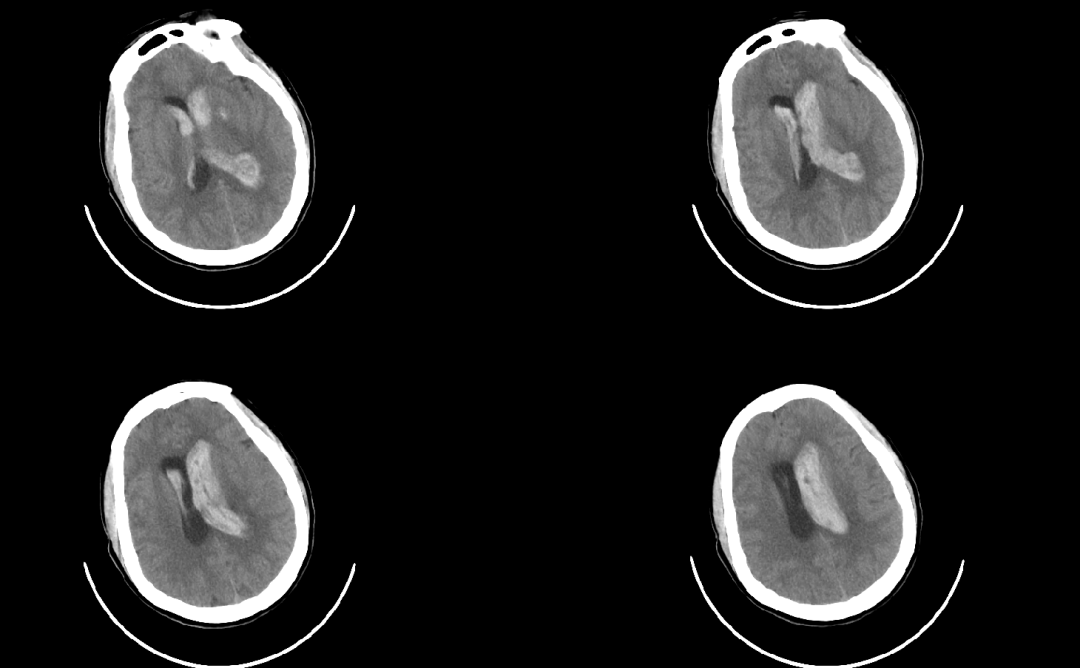

病例3

患者66歲女性,因“被發(fā)現(xiàn)不省人事3小時”急診入院,被診斷為“腦出血”?;颊叩难[占位效應明顯,出現(xiàn)神經(jīng)功能障礙,手術指征明確,手術團隊充分評估后為其進行微創(chuàng)手術治療,目前生命體征平穩(wěn),正在康復中。